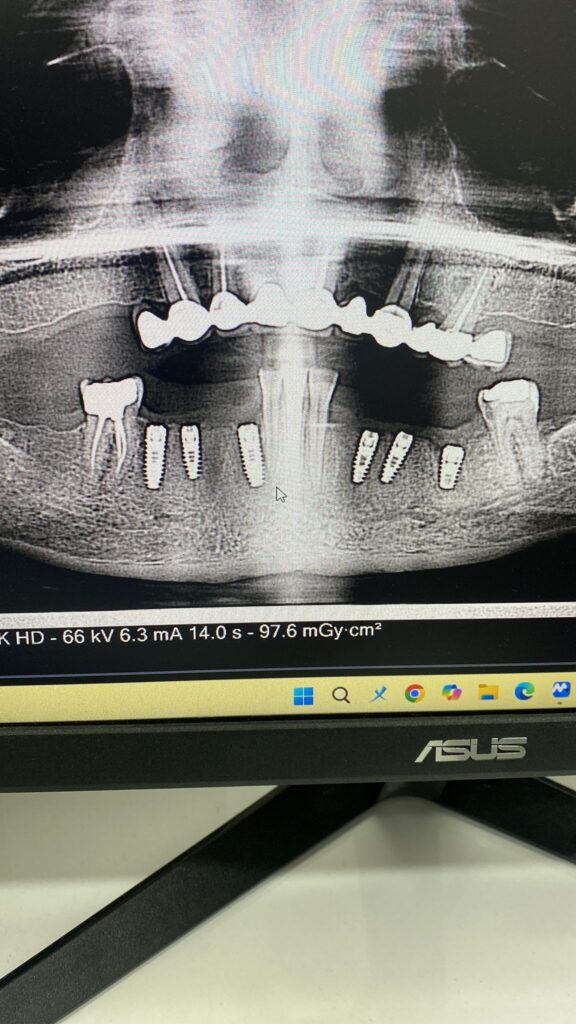

İmplantoloji

Kaybettiğiniz dişlerin yerine doğal ve fonksiyonel implant çözümleriyle eksiksiz bir gülüşe kavuşmanızı sağlıyoruz